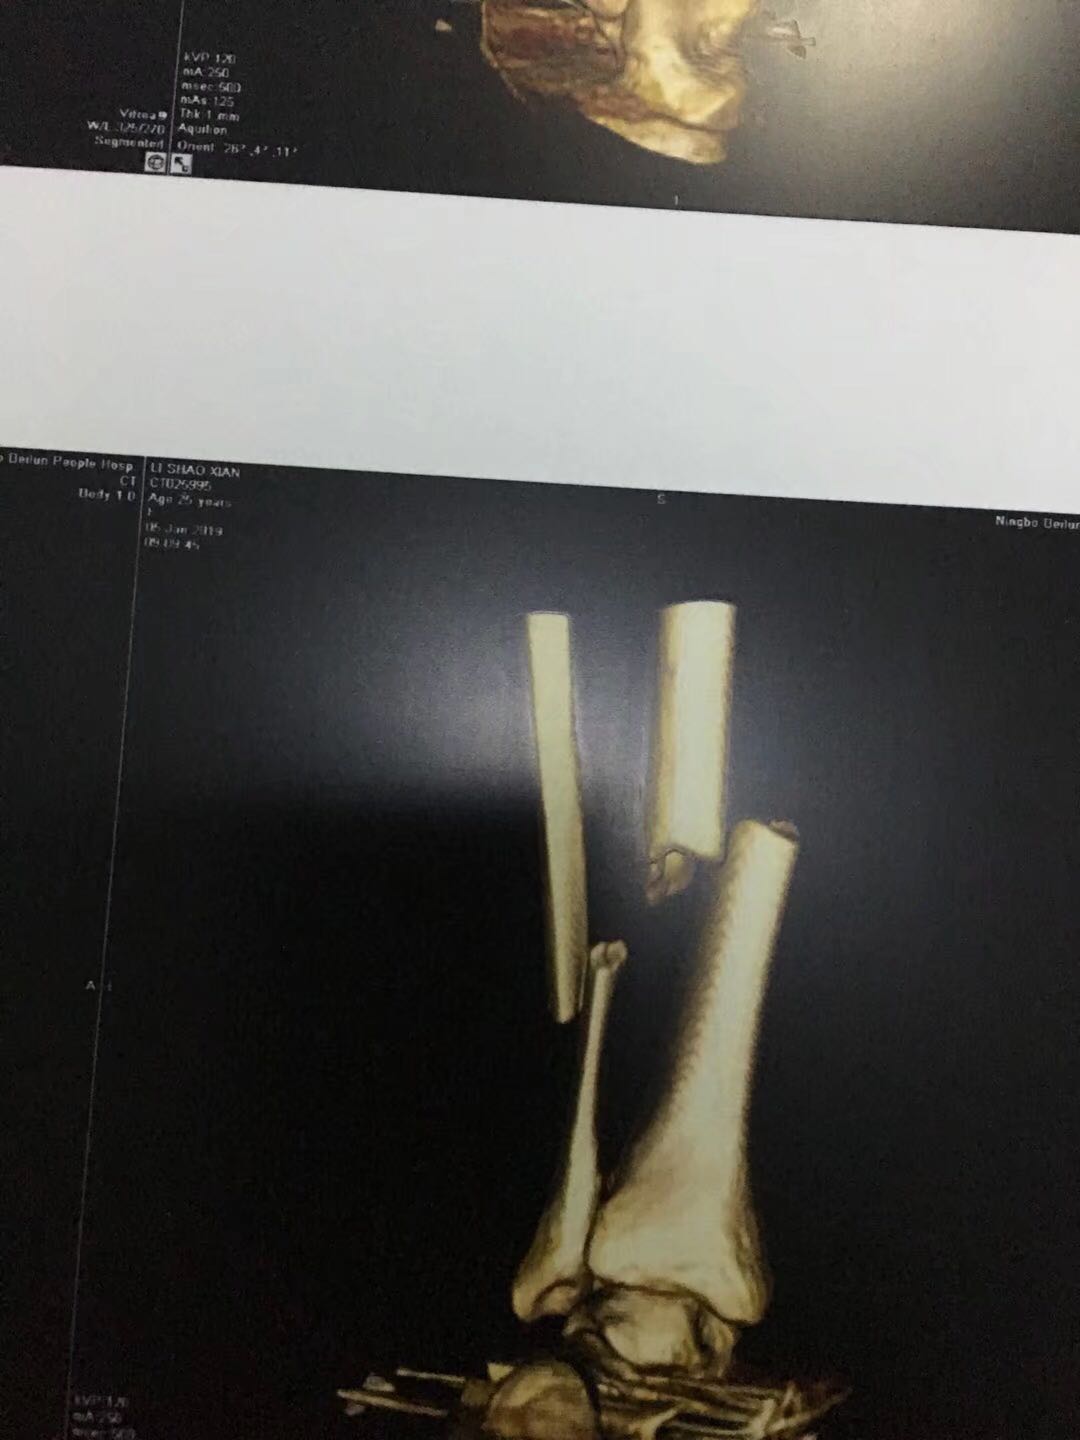

浙江宁波交通事故小腿2根骨头骨折 能鉴定上吗 今天1月份的车祸

可以的,打底十级

你这个危险,不是关节部位评不到

看地区,有的给,有的不给,因为这种情况以双下肢相差2cm为十级。一般这种情况脚不会相差两个分